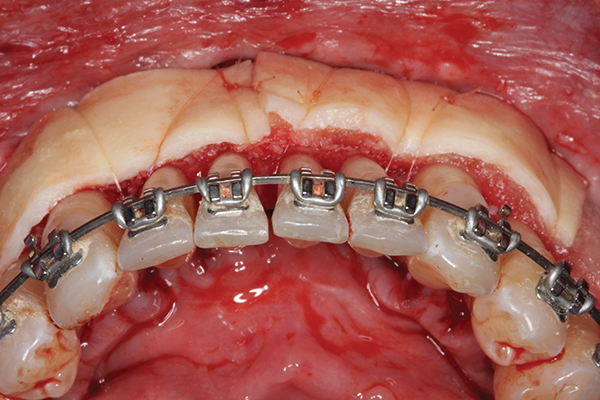

Fig 4. Particulate corticocancellous mineralized freeze-dried bone allograft in place on the left half of the mandible for periodontal regeneration and alveolar augmentation.

Figure 4

Fig 5. Bone grafting complete. Collagen wound dressing in place for graft stabilization and autogenous connective tissue grafts in

place, teeth Nos. 21 and 22 and Nos. 27 and 28, for simultaneous soft-tissue augmentation.

Figure 5